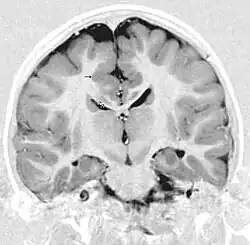

Gray matter heterotopia

Gray matter heterotopia is a neurological disorder caused by gray matter being located in an atypical location in the brain.[1]

Detection of heterotopia generally occurs when a patient receives brain imaging—usually an MRI or CT scan—to diagnose seizures that are resistant to medication. Correct diagnosis requires a high degree of radiological skill, due to the heterotopia's resemblance to other masses in the brain.